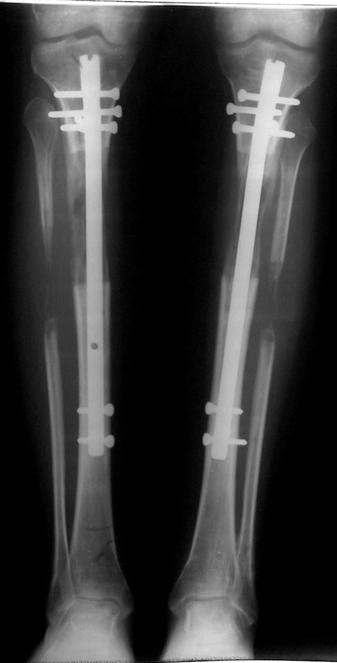

Biz son zamanlarda, seçilmiş vakalarda, uzatma sonrası uzunluğu ve “alignment’ı” korumak amacı ile unilateral dinamik aksiyel fiksatör ve kilitli intramedüller çivi kombinasyonunu tercih etmekteyiz. Bu yöntemin ön şartları medullanın en dar çapının 7 mm.’den geniş olması ve uzatma sonrası distalde en az 8 cm. uzunluğunda çivi kalabilmesidir. İntramedüller çivi hem uzatma esnasında femurun üzerine gelen makaslama ve bükülme kuvvetlerini nötralize etmekte hem eksternal fiksasyon süresini kısaltmakta, hem de yeni oluşan kemiği kırıklara karşı korumaktadır. Serimizde bir vakada subtrokanterik femoral osteotomi yapılmıştır. İntramedüller çiviye rağmen varus angulasyonu oluşması yönünde bir dezavantaj tespit etmedik.

İlizarov, distraksiyon osteogenezisi için endosteal kan dolaşımının önemini vurgulamıştır. Biz tüm vakalarımızda femuru oyarak intramedüller çiviyi çaktık; buna rağmen hiçbir vakada kallus oluşma süresi tahminimizden daha uzun olmadı. Bu yüzden medüller dolaşımın bozulmasına bağlı yeni kemik oluşma hızında bir yavaşlama olmadığını düşünüyoruz. Oyma sonrası meydana gelen revaskülarizasyon, intramedüller çivili fiksasyon stabilitesi ve erken fonksiyonel yüklenme bu gerçeğin temelini oluşturmaktadır. Eksternal ve internal fiksasyon yöntemlerinin kombine kullanımının potansiyel dezavantajları kan kaybının artması, intramedüller infeksiyon, yağ embolisi olasılığı ve aşırı metal yüküdür. Bunların içinde en çok korkulan problem bir çivi dibi infeksiyonun tetikleyeceği derin intramedüller infeksiyondur (panosteomyelit). Bizim serimizde bu yönde hiçbir komplikasyon gelişmemiştir. Bu olası komplikasyonun önlenmesi amacı ile uzatma sonundaki kilitleme medialden yapılmalıdır; ayrıca intramedüller çivi ve eksternal fiksasyon pinlerinin teması önlenmelidir.

İntramedüller çivi ve eksternal dinamik aksiyel fiksatör kombinasyonu teknik olarak standart İlizarov uygulamalarından daha zordur. Ancak şu avantajlar yöntemi cazip hale getirmektedir; eksternal fiksasyon süresinde kısalma, refraktüre karşı korunma, erken rehabilitasyon, azami hareket genişliği kazanma ve günlük yaşam konforu. Bu avantajlar artan maliyet , artan kan kaybı ve potansiyel derin infeksiyon gibi dezavantajların önüne geçmektedir. Sonuç olarak, bulgularımızın eşliğinde, intramedüller çivi üzerinden femoral uzatma tekniğinin güvenilir ve dayanıklı bir metod olduğunu ve bizce standart İlizarov uygulamalarına üstünlük sağlayan avantajlar getirdiğini söyleyebiliriz.